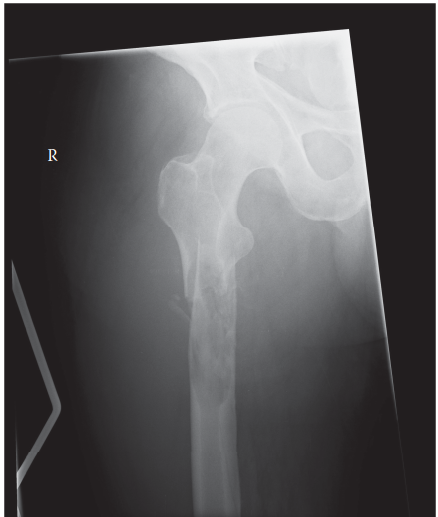

Can you describe the radiograph? This is an AP radiograph of the right hip. There is a pathological fracture …